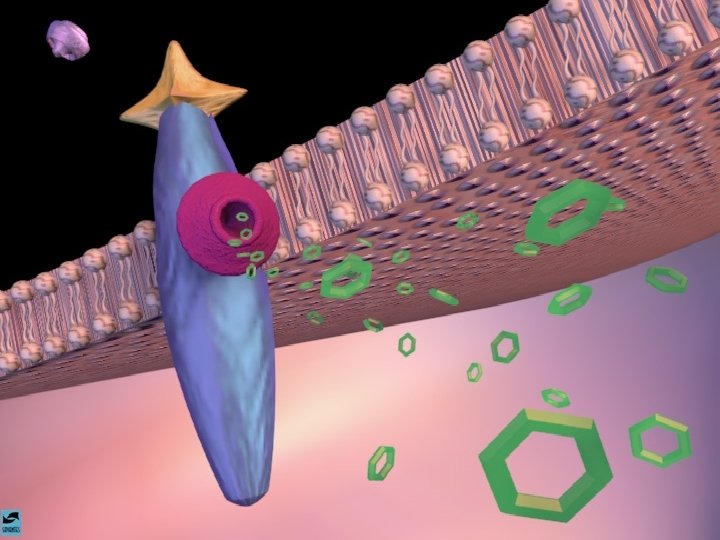

A AÇÃO DAS DROGAS NO SISTEMA NERVOSO CENTRAL A SINAPSE

A AÇÃO DAS DROGAS NO SISTEMA NERVOSO CENTRAL OS NEUROTRANSMISSORES - NORADRENALINA - SEROTONINA - DOPAMINA - GABA - ACETILCOLINA

OS OPIÁCIOS EFEITOS CEREBRAIS OS OPIÁCIOS LIGAM-SE AOS RECEPTORES CEREBRAIS DE ENDORFINAS